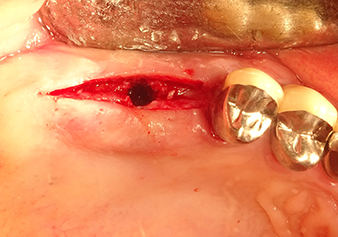

Подготовка ложа имплантата и наращивание

После промежуточного контроля (рис. 4) был проведен еще один этап подготовки (рис. 5). За тем, с помощью гидравлического инструмента Z35P мембрана была поднята в нужное положение (рис. 6 и 7). Далее, следовала дальнейшая пьезохирургическая подготовка ложа для имплантата, завершенная с помощью ротационного бора и лопаточной фрезы до диаметра имплантата 4,8 мм. Перед установкой имплантата под мембрану Шнейдера был введен аугментационный материал (размер частиц около 0,8-1,6 мм) (рис. 8).

Имплантация и протезирование

Для перемещения аугментационного материала в направлении верхнечелюстной пазухи атравматично, имплантат вводился очень медленно вручную (рис. 9). При этом мембрана еще раз выталкивалась в краниальном направлении. Через два месяца место операции зажило без раздражения. Через шесть месяцев рентгеновский контроль показал значительное увеличение помутнения, что свидетельствует об оссификации (рис. 10). Протезирование было проведено металлокерамической коронкой.